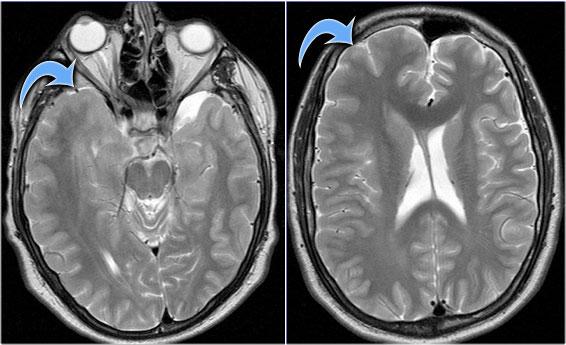

Hình ảnh của bệnh nhân nam 27 tuổi bị động kinh thùy chẩm kháng trị.

Ảnh FLAIR mặt phẳng coronal và T2W mặt phẳng axial cho thấy dày vỏ não tăng tín hiệu T2 và tăng tín hiệu ở vỏ não và vùng dưới vỏ.

Lưu ý vùng tăng tín hiệu dưới vỏ kéo dài đến não thất bên phải, biểu hiện dấu hiệu xuyên vỏ (mũi tên xanh).

Dấu hiệu xuyên vỏ (transmantle sign) ghi nhận ở một bệnh nhân khác bị loạn sản vỏ não khu trú.

Chuỗi xung T1W cho thấy hình ảnh so sánh giữa cấu trúc phân lớp và rãnh não bình thường ở bên trái và hình ảnh đa tiểu hồi não ở bên phải (mũi tên).

Hình ảnh của một trường hợp dị sản vị dưới màng nội tủy điển hình.

Một trường hợp dị sản vị khác với các nốt dưới vỏ não điển hình (mũi tên).